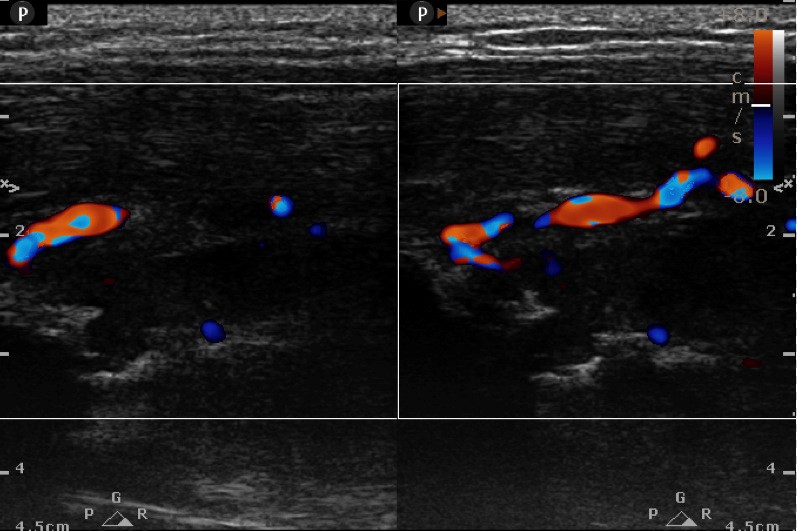

GRANULATION STAGE: soft hypoechoic callus + >5 vs + R.I. 0.50-0.70---2 wk

FIBROUS STAGE: Organized callus echo T.A.Ms. + vs ….3 wks

First screen USG at 4 weeks

CARTILAGENOUS STAGE: Long. oriented parallel to the fracture ends with speckled dots of mineralization+ vascularity…4 wk

OSSEOUS STAGE : Echogenic callus with acoustic shadowing and obscured medullary cavity / IM nail …5-6 wks

Fracture of long bones and in particular of tibia has remained a bane for most of the orthopedicians since they land up with frequent delayed and non-unions. Till date there is no modality except a skiagram which can predict union but not before 12 weeks... High frequency ultrasound has come to establish itself as the modality which can predict delayed union as early as 4 weeks and non-union at 7-8 weeks. Interlocking which is the mainstay of management for fracture shaft tibia today can be effectively managed early by dynamizing at 4weeks in case of delayed union , or in case of infections reaming with exchange nail at 6 weeks to save the patient the catastrophe of a non-union or osteomyelitis. Both grey scale imaging and colour doppler imaging act in a symbiotic manner to give a high predictability rate for union/ nonunion or delayed union in cases of fracture healing.